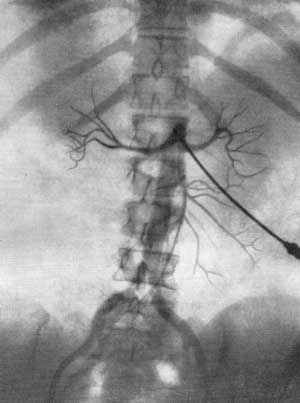

В результате серийной почечной ангиографии представляется возможность судить о четырех фазах циркуляции контрастной жидкости в почке и мочевых путях. Вначале получаем изображение почечных артерий и их ветвей — артериограмму (рис. 3), затем — изображение почечной паренхимы в виде плотной тени — нефрограмму (рис. 4), далее удается зафикси- ровать момент оттока по венам контрастной жидкости — венограмму и, наконец, экскреторную урограмму. Изучение всех стадий циркуляции контрастной жидкости в почке имеет большое диагностическое значение (рис. 5, 6 а, б).

Р

ис. 3. Почечная ангиография (транслюмбальный метод). Мужчина 39 лет. Артериографическая фаза. Нормальные почечные артерии и их ветви.Рис. 4. Почечная ангиография (транслюмбальный метод). Мужчина 39 лет. Нефрографическая фаза. Нормальная функция почек.